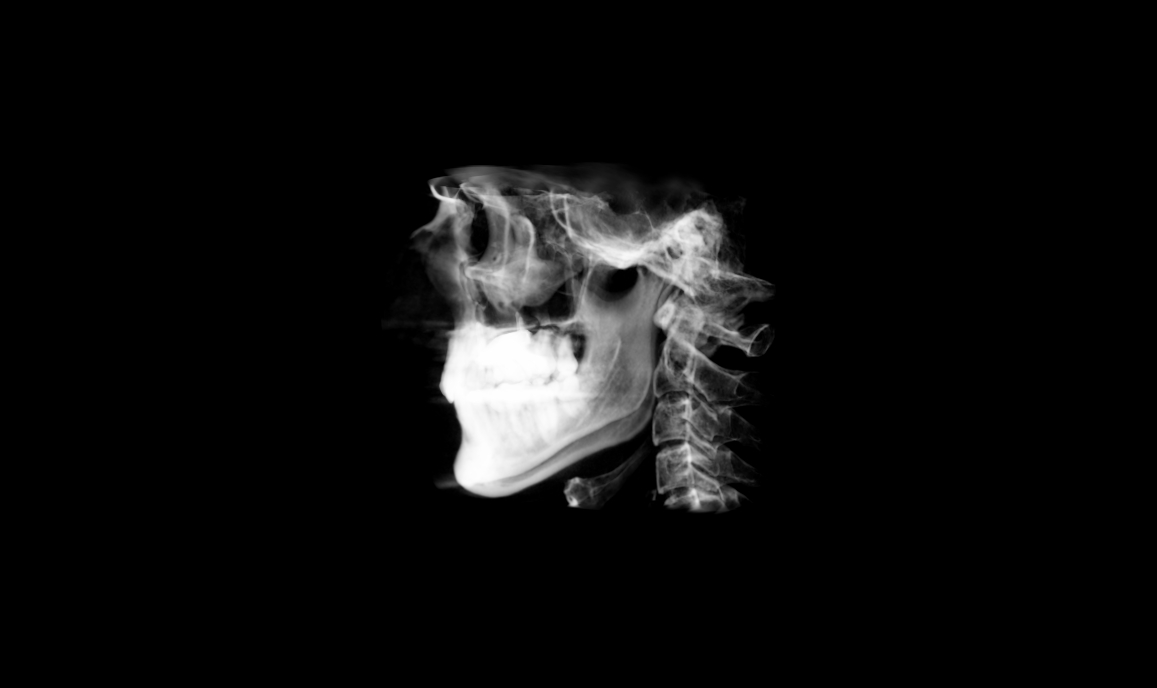

CBCT:

Panoramic. My LR8 (lower right 8/third molar/wisdom tooth) is mesially (towards the center line) inclined and impacted here. We’re attempting to upright it with Invisalign as of April 2026.